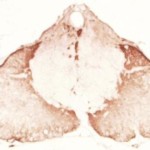

Se un bambino nasce con la miopatia miotubulare, la forma più grave di miopatie centronucleare (chiamata anche XLCNM), è appena in grado di respirare autonomamente.

Questo tipo di trasporto è bloccato nei pazienti XLCNM, come è stato dimostrato da Katharina Ketel del gruppo Haucke, con esperimenti intricanti e immagini ad alta risoluzione dell’interno della cellula. La causa della malattia è un difetto di MTM1, un enzima che rimuove gruppi fosfato dai PIP e funziona solo in collaborazione con un altro enzima che attribuisce un gruppo fosfato ad un altro sito sulla testa idrosolubile di PIP. Questo chiarisce come i processi dinamici sono diretti nelle cellule e illustra come studiare una rara malattia genetica può scoprire un meccanismo molecolare essenziale per le nostre cellule, per funzionare correttamente.

“Nei pazienti XLCNM, alcuni dei contenitori di trasporto di sostanze da trasmettere originariamente alla superficie cellulare, restano bloccati all’interno della cellula perché un gruppo fosfato non può essere rimosso da un certo PIP” dice Jocelyn Laporte, un esperto in XLCNM e collaboratore dello studio. “Nei muscoli, questo può significare che le proteine necessarie per la loro formazione, l’integrità e la funzione non si trovano al posto giusto nella cellula”. Nei loro esperimenti in coltura cellulare, i ricercatori hanno potuto riavviare il trasporto con una certa sostanza attiva.Questo potrebbe essere un punto di partenza per lo sviluppo di farmaci per il trattamento di questa malattia ereditaria grave e attualmente incurabile.